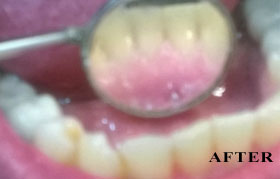

PHOTO GALLERY

Cosmetic, Reconstructive & Athletic Dental Surgeon - Smile Design / Implants